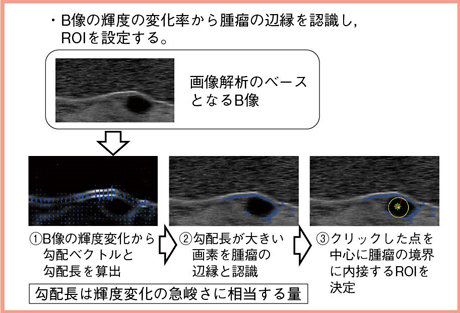

Assist Strain RatioのROI決定のアルゴリズムは,次のとおりである。腫瘤ではまず,Bモード画像の輝度の変化率に着目し,急激に輝度が変わる(勾配長が大きい)ところを腫瘤の辺縁と認識する。そして,腫瘤の中心をクリックすると腫瘤の辺縁までの内接円を取ったROIが設定される(図4)。

図4 ROI(腫瘍)決定のアルゴリズム